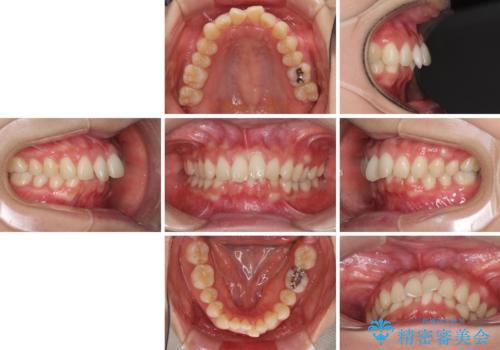

インビザラインによるディープバイトの改善

- 口元の前突感と深い咬み合わせ(ディープバイト)を気にして来院された患者様です。

インビザラインによる上下歯列の遠心移動(後方移動)と、それに伴う近心傾斜(前方傾斜)の改善により、口元の突出感とディープバイトを改善することとしました。

前歯のデコボコを最も気にしていましたが、咬み合わせが深く歯ぎしりが自由にできない点を指摘すると、常に食いしばってしまうことも悩みであることが分かりました。

咬合状態が大きく変化したため、治療後半では咬み合わせの位置が定まらなくなりました。上下の前歯に後戻り防止用のワイヤーを装着し、奥歯の咬合をフリーにしたことで1ヶ月ほどで咬み合わせが定まりました。